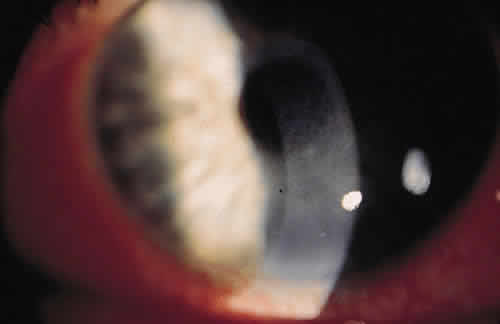

For the factors of innate immunity to be available at the site of potential infection, the factors must be brought to the area of interest through the bloodstream. The acute inflammatory response to bacteria or tissue injury is characterized by capillary dilation and increased capillary permeability. This transfers to the conjunctival epithelium the neutrophils, which play a crucial role in the defense against pyogenic bacteria, such as pneumococci and streptococci. In addition to furthering the transfer of leukocytes, the increased capillary permeability brings about a massive transudation of bactericidal factors contained in the serum: C-reactive protein, defensins, properdin, and the complement system (Fig. 1). These factors aid in the adherence of bacteria to the polymorphonuclear leukocyte and ultimately in phagocytosis.2 Defensins, for example, are considered to be one of the earliest peptide effectors of innate immunity.15 They are released by neutrophils and are present in tears and in the ocular mucosa.16 Defensins have antimicrobial activity against gram-positive and gram-negative bacteria, fungi, and viruses and accelerate wound healing by their mitogenic effect on epithelial cells and fibroblasts.